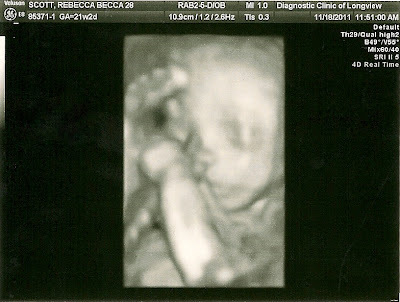

| Here's a straight on view of her face & stomach. We are really looking forward to our 4D ultrasound in a week & half! |